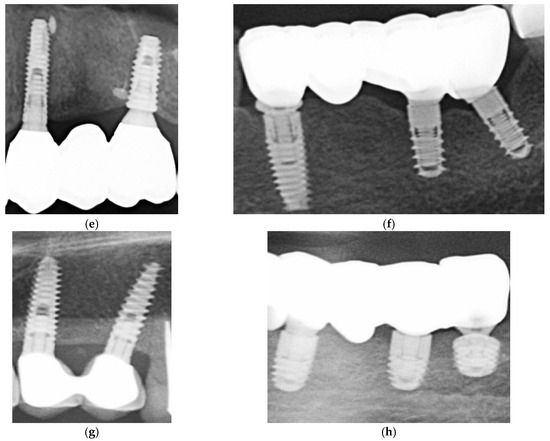

In Figure 1 are presented two cases, one cemented with Fuji Plus and one with DentoTemp™.

Figure 1. Sections of orthopantomographs (OPGs) showing two cemented partial restorations monitored between 2020 and 2025. The left panels depict a metal–ceramic three-unit prosthesis cemented with DentoTemp™, while the right panels show a zirconia three-unit prosthesis cemented with Fuji Plus®. Images are arranged chronologically from baseline (2020) to the most recent control (2025), illustrating stable peri-implant bone levels in both groups.